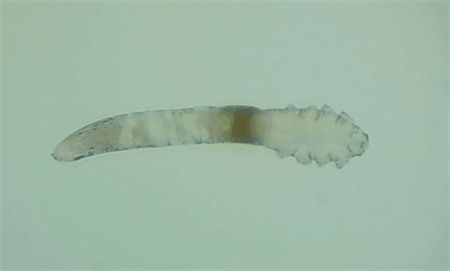

5、螨蟲檢查

從每只眼上(眼瞼)拔3根睫毛,在顯微鏡下觀察是否存在蠕形螨,以及數(shù)量多少。

如果任意一個眼瞼螨蟲數(shù)量≥3只,就需要除螨治療了。眼瞼螨蟲過多會造成機(jī)械性損傷,附帶細(xì)菌還會引起瞼緣感染,后續(xù)會有干癢、紅腫、分泌物增多、睫毛脫落等一系列問題。